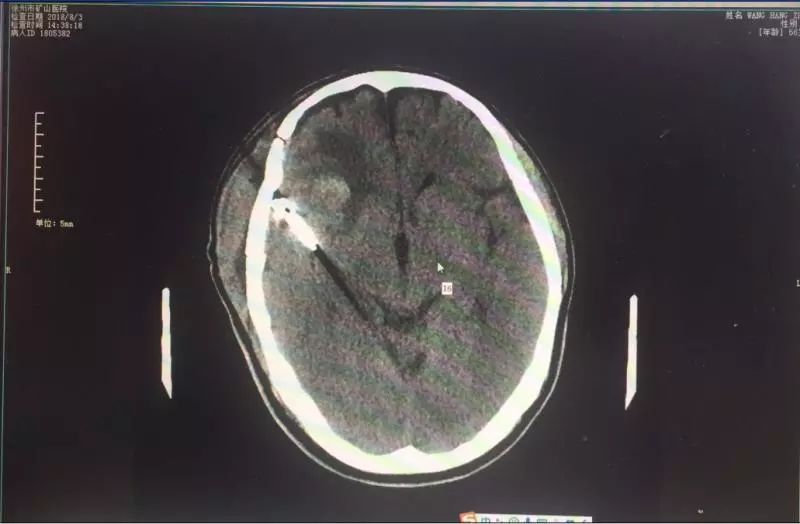

入院后,行頭顱MRI示:右側(cè)大腦中動(dòng)脈分叉部動(dòng)脈瘤;頭顱CTA示:右側(cè)大腦中動(dòng)脈分叉部動(dòng)脈瘤,動(dòng)脈瘤約9.0mm*8.5mm大小,寬頸。礦山醫(yī)院神經(jīng)外科高立志主任告訴王先生的家人,腦動(dòng)脈瘤并非真正的腫瘤,而是由于腦動(dòng)脈內(nèi)腔的局限性異常擴(kuò)大造成動(dòng)脈壁的一種瘤狀突出。由于起病急、癥狀重,被稱為“顱內(nèi)不定時(shí)炸彈”。

對(duì)于動(dòng)脈瘤患者來說,時(shí)間就是生命。經(jīng)家屬同意后,高立志主任決定立即為王先生行開顱動(dòng)脈瘤夾閉術(shù)。手術(shù)持續(xù)了約兩個(gè)小時(shí),非常成功。術(shù)后王先生逐漸康復(fù),生命體征平穩(wěn),無神經(jīng)功能缺失,一周后平安出院。